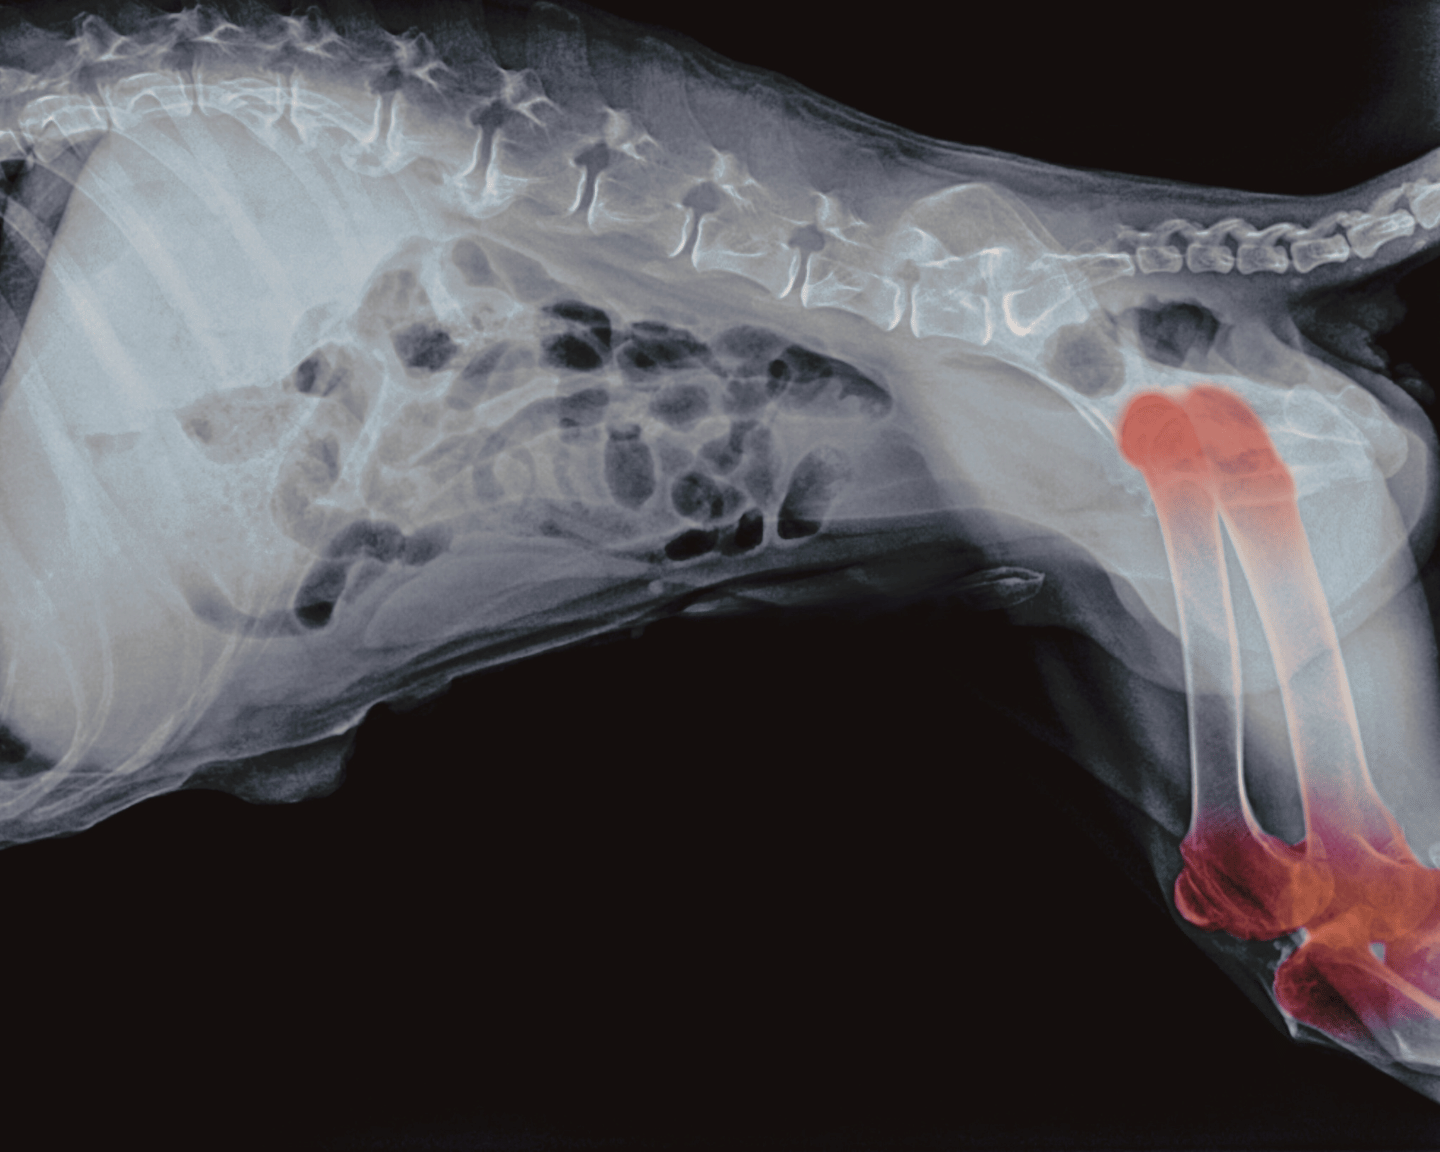

Why Joints Are Often the First to Show It

Joint tissue is highly sensitive to inflammatory damage. When inflammatory signaling remains elevated:

• Cartilage degrades faster

• Synovial fluid quality declines

• Movement becomes uncomfortable

This is why diet and joint health are inseparable.